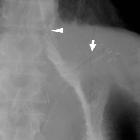

Perirenal

neoplastic recurrence from adenocarcinoma of the gastric cardia. A few days after surgery, upper gastrointestinal series with water-soluble contrast showed complete gastrectomy with patent Roux-en-Y anastomosis (arrowhead). Note drainage tube in place (short arrow).